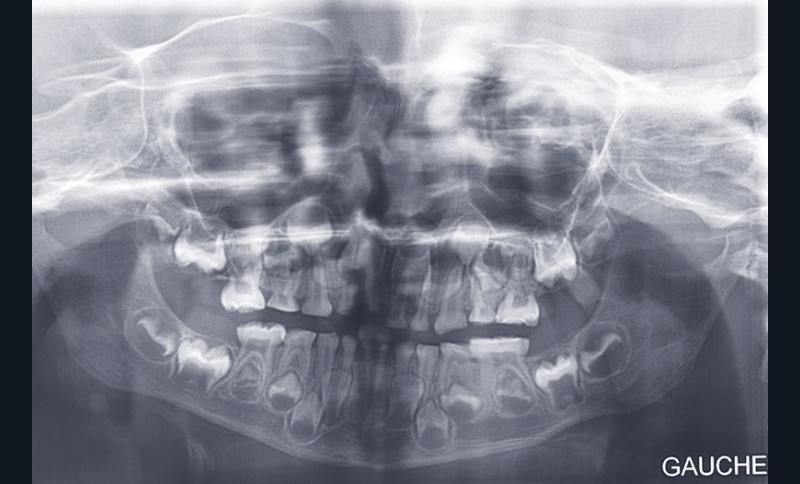

Teinte opalescente grise à jaune ambrée, couronnes globuleuses, calcifications intra-pulpaires, racines fines et courtes, attrition précoce, nécrose aseptique… Ces anomalies cliniques et radiographiques décrivent le tableau de la dentinogenèse imparfaite (DI) isolée de type 2. Cette anomalie génétique à transmission autosomique dominante est liée à un défaut de DSPP, gène de la sialophosphoprotéine dentinaire [1, 2]. Des anomalies dentinaires similaires résultent également de mutations de ce gène. Les avancées en recherche génétique tendent à réunir ces pathologies sous une même étiologie.

Un diagnostic précoce est primordial, car il existe aussi une forme associée à une anomalie osseuse, l’ostéogenèse imparfaite. Le chirurgien-dentiste est donc au premier plan pour dépister ces anomalies et limiter dès le plus jeune âge leurs conséquences infectieuses, fonctionnelles et esthétiques.

Shield [3] a proposé en 1973 une classification fondée sur des différences phénotypiques. Il distingue les anomalies dentinaires isolées des anomalies dentinaires syndromiques (tableaux 1 et 2).